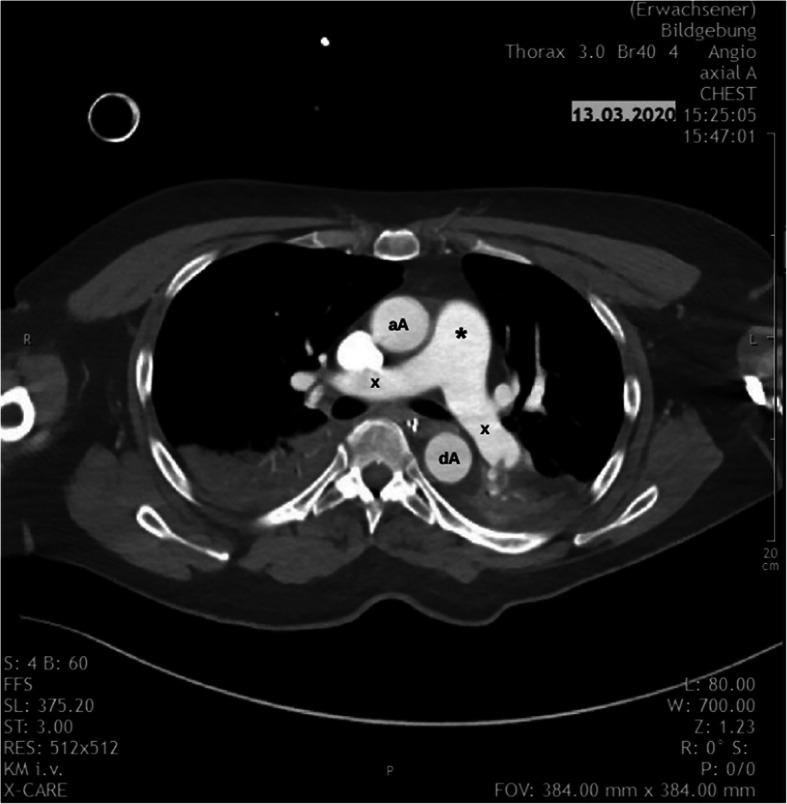

CASE PRESENTATION

We report two cases of high-risk perioperative PE. Both patients developed severe haemodynamic instability leading to cardiac arrest. After the implantation of a veno-arterial extracorporeal membrane oxygenation (ECMO), they were both successfully treated with USAT. Adequate improvement of right ventricular function was achieved; thus, ECMO could be successfully weaned after 3 and 4 days, respectively. Both patients showed favourable outcomes and could be discharged to rehabilitation.

病例报告

我们报告两例围手术期高危PE病例。两名患者均出现严重血流动力学不稳定,导致心脏骤停。在植入静脉-动脉体外膜肺氧合(ECMO)后,他们均成功接受了USAT治疗。右心室功能得到充分改善;因此,ECMO分别在3天和4天后成功撤机。两名患者均预后良好,可出院接受康复治疗。